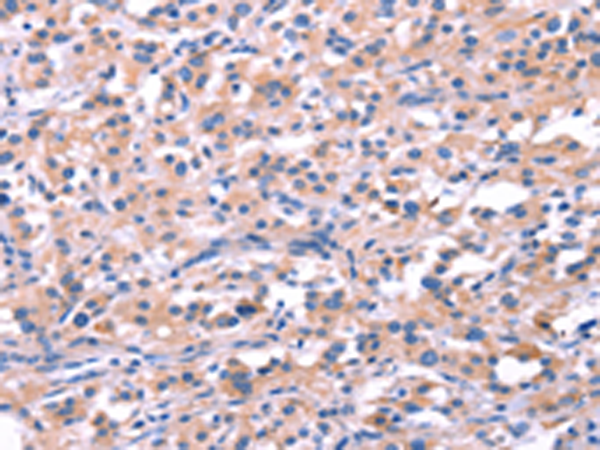

分类: 科研抗体货号: P04914别名: H963应用: WB,IHC反应种属: Human